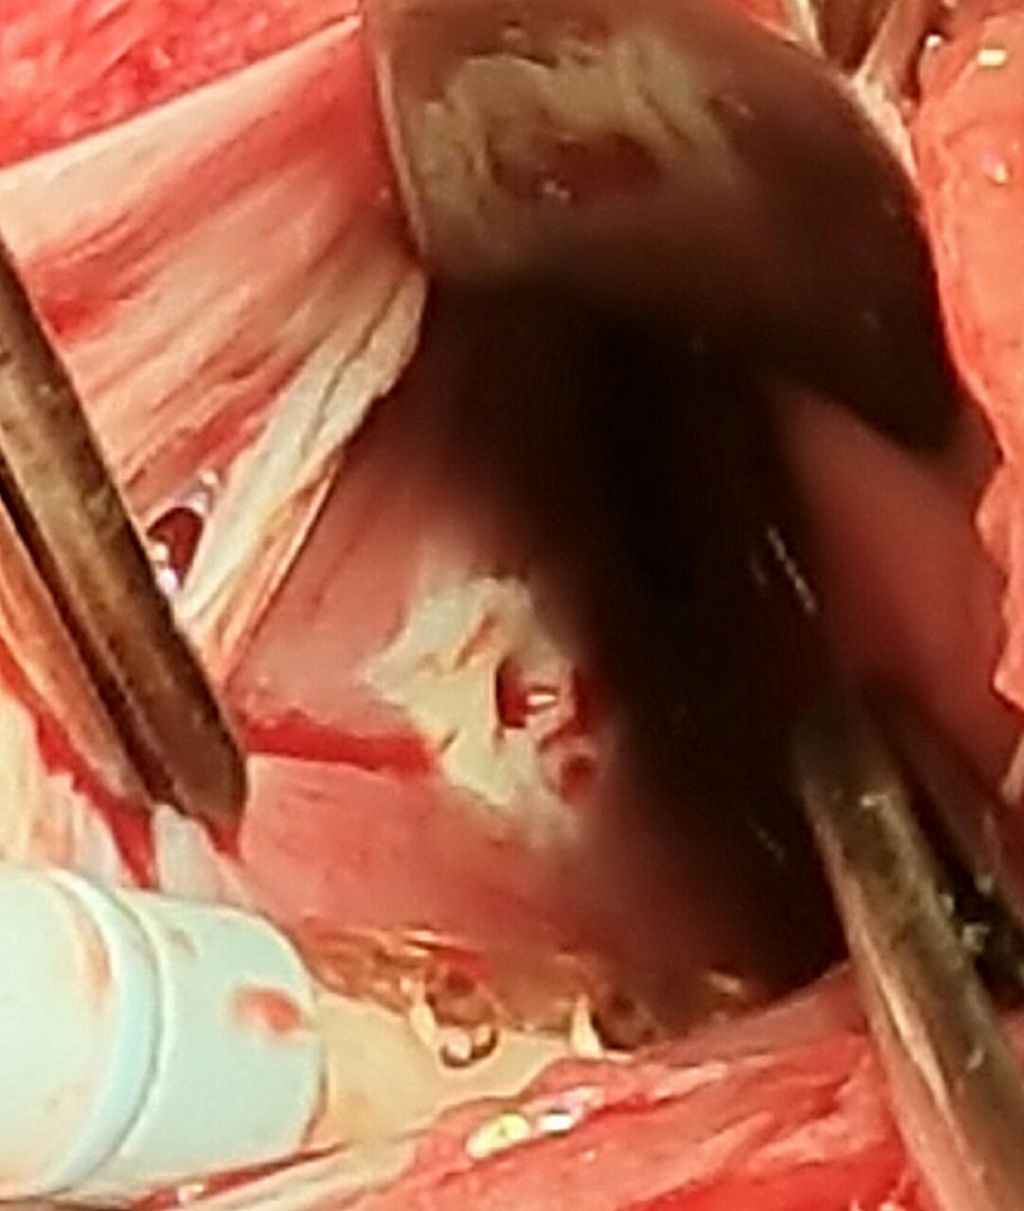

La directora Asistencial del Hospital Interzonal San Juan Bautista, la Dra. Silvia López, confirmó la realización de una cirugía cardíaca de alta complejidad practicada ayer martes 8 de noviembre a una paciente que sufrió una herida de arma blanca.

López además destacó la colaboración del jefe de Cirugía Cardiovascular del Hospital Austral de Buenos Aires, el Dr. Guillermo Vaccarino que arribó a nuestra provincia para participar de la cirugía, y trabajó junto al equipo local del Hospital  San Juan Bautista liderado por el cirujano cardiovascular, el Dr. Fernando Fedullo; la colaboración también, del cirujano cardiovascular, el Dr. Pablo Marin; el cirujano de Tórax, el Dr. Edgar Reartes y el anestesiólogo, el Dr. Marcelo Gómez.

López señaló que se trata de una cirugía muy compleja que requiere de la intervención de un equipo interdisciplinario altamente capacitado.

Finalmente, la Dra. López informó que la paciente que sufrió la herida de arma blanca en marzo pasado, (oportunidad en la que se le salvó la vida) quedó con secuelas que finalmente fueron resueltas ayer  tras la intervención. La paciente  cursa un post operatorio favorable en la Unidad Coronaria del nosocomio local.